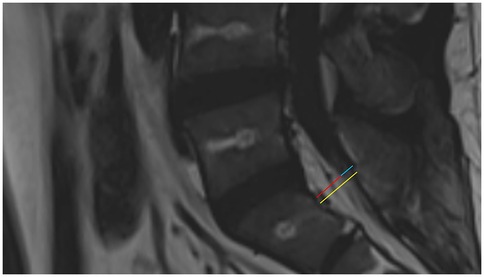

SEL is a neurological condition caused by excessive adipose tissue within the spinal canal compressing the surrounding dura mater and nerve structures. Its clinical symptoms lack specificity and may include chronic pain in the lower back and limbs, numbness in the lower limbs, and decreased sensation. In severe cases, SEL can lead to cauda equina syndrome or even paralysis (2). Common causes currently include long-term use of exogenous steroids, exposure to endogenous steroids, obesity, surgical induction, and idiopathic diseases (3, 4). Diagnosis primarily relies on MRI, which is considered the gold standard(5). The thickness of epidural fat in normal individuals is usually between 3 and 6 mm in the sagittal plane (6). Objective grading of excess epidural fat in patients with lumbar SEL is usually based on the MRI grading proposed by Borré et al.in 2003 (7). Grading is performed on an axial plane that is parallel and tangent to the superior endplate of the vertebral body, and the following three measurement values are obtained: anteroposterior maximum diameter of the dural sac (DuS), anteroposterior maximum diameter of the epidural fat (EF), and anteroposterior maximum diameter of the spinal canal (SC). With these values, the DuS/EF and EF/SC indices can be calculated. Details of the grading are shown in Table 2 (7, 8). In this case, the patient’s measurements for SC, EF, and DuS were 15.48 mm, EF: 10.40 mm, DuS:5.08 mm, respectively, resulting in calculated DuS/EF and EF/SC indices of 0.49 and 67%, respectively. Thus, according to the classification criteria, the patient’s SEL was Grade II (Figure 4). This report highlights the pelvic floor electrophysiological findings in SEL and documents two sets of electrophysiological data corresponding to different stages of disease progression.

Figure 4. Sagittal T2 FLAIR MRI of the patient. The yellow line shows the anteroposterior maximum diameter of the spinal canal, the red line shows the anteroposterior maximum diameter of the epidural fat, and the blue line shows the anteroposterior maximum diameter of the dural sac.